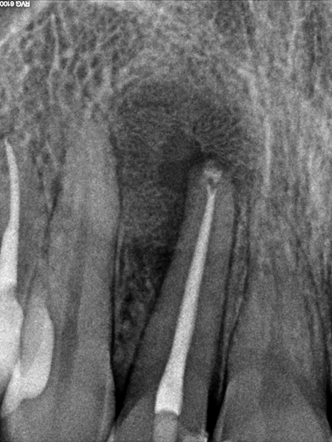

- Проходим корневые каналы специальным инструментом и расширяем их до круглого сечения. При этом применяется ЭДТА для частичной деминерализации и облегчения прохождения.

- Промываем каналы горячим раствором гипохлорита натрия. Это который «Белизна», только чистый, каталитического происхождения и другой концентрации. Стоматолог в каждый канал специальным ирригатором вводит тёплый раствор, который убивает любую органику, затекает в микрощели и ответвления. В определённых техниках это может сочетаться с ультразвуком как в УЗ-ваннах для отмывки плат и ювелирных изделий.

- Остатки гипохлорита вымываем стерильным физраствором и хлоргексидином высокой концентрации. В идеале на этом этапе мы должны убрать весь детрит, опилки и остатки погибших в хлорке бактерий на всём протяжении канала.

- Закладываем лечебную пасту на базе гидроксида кальция. Это щёлочь, которая очень быстро убьёт всех оставшихся бактерий, пропитает дентин и частично выйдет за пределы верхушки корня. За счёт щелочной среды и избытка ионов кальция произойдёт стимуляция остеобластов, которые начнут выращивать кость на месте дефекта, созданного кистой. Лечебная паста обычно остаётся на 14 дней.

- Через 14 дней ещё раз промываем всё гипохлоритом и хлоргексидином, после чего пломбируем канал, стараясь заполнить все боковые ответвления.

Для того чтобы решить проблему, мы пошли на резекцию верхушки корня. При этом стоматолог-хирург получает доступ к корню с обратной стороны, через кость. Под анестезией осторожно откидывается слизисто-надкостничный лоскут, перфорируется кость, и хирург получает возможность непосредственно удалить проблемную верхушку корня и специальным инструментом вычистить всю полость. Затем доступ в корневой канал закрывается пробкой из специального материала (белое пятнышко у верхушки корня). Всё промывается антисептиком, после чего ушивается.